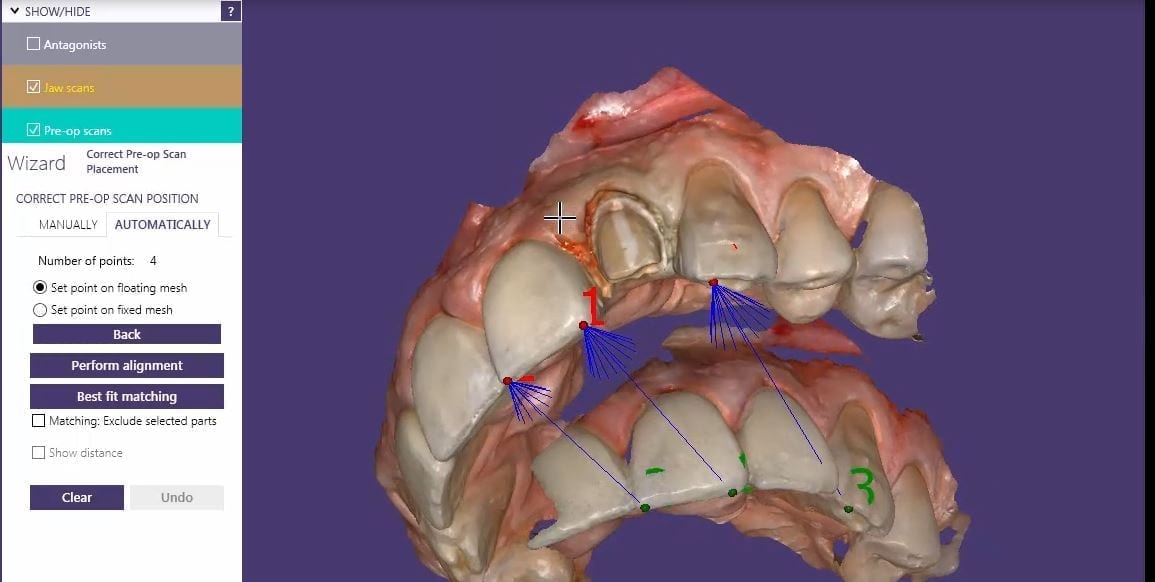

You can then launch a second case, where you take the opposing, the prepared arch, and the buccal bite images. You can download the Korolation OBJ case files and design along. Just remember, in exocad, the upper and lower arches from “patient #2″ will automatically articulate with each other, but you will have to manual import the preop scan and merge the prepped model and the pre-op models.

Once you import in the pre-op condition, you can manually relate the models to each other by identifying common landmarks between the two models. After you perform alignment, you can then click on “Best fit matching”. The color scheme in exocad is a great guide in letting you know how well you have articulated the models together.